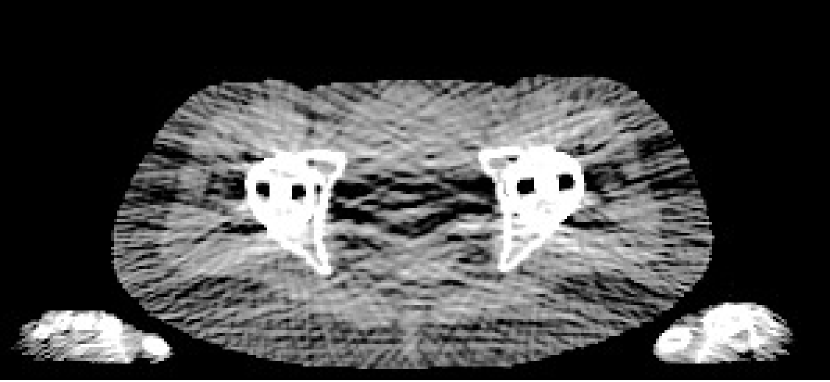

4.3 Cone-Beam CT Validation

To validate our method, we also tested its ability to perform quantitative reconstruction from real X-ray cone-beam CT (CBCT) measurements. For this, we acquired a scan with a Varian® TrueBeam™ On-Board Imager® of a CIRS STEEV head phantom. The phantom consists of synthetic resins to mimic the attenuating properties of human tissues, allowing quantitative assessment of relative electron density accuracy. There was also a metal structure in the centre of the phantom, consisting of the plug section from a PTW PinPoint® ionisation chamber, allowing us to investigate the mitigation of metal induced artefacts.

4.3.2 CBCT Reconstruction

For reconstruction, we mapped into a resolution of 512×512×144512512144512\times 512\times 144, and used each method as detailed in Section 4.2.1. We ran each iterative method for 500 iterations. For the regularisation parameter, we heuristically used 0.5λpelvis0.5subscript𝜆pelvis0.5\lambda_{\textrm{pelvis}}, where λpelvissubscript𝜆pelvis\lambda_{\textrm{pelvis}} were the same TV regularisation parameters from the digital pelvis experiment, and gave good empirical performance on the CBCT data. Finally, for the bone and metal segmentations required for Poly-SIR, we obtained these through applying thresholds on the FBP and PWLS separately. To illustrate the critical role of this step, we have shown both images in Figures 11(c) and 11(d).

Refer to caption

(a) FBP CBCT

(b) PWLS CBCT

(c) Poly-SIR CBCT 1

(d) Poly-SIR CBCT 2

(e) IMPACT CBCT

(f) Polyquant CBCT

Figure 11: Results from electron density reconstruction from real CBCT data showing slice 83, where each is shown with display window [0.7,1.4]: (c) is Poly-SIR given a bone and metal segmentation derived from the FBP; (d) uses a segmentation derived from the PWLS